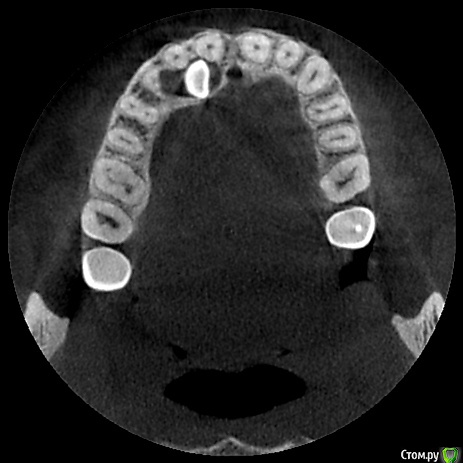

natalie_summerwhile Опубликовано 10 июля, 2017 Автор Поделиться Опубликовано 10 июля, 2017 Во рту вместо клыка молочный Ссылка на комментарий

Qvonti Опубликовано 12 декабря, 2018 Поделиться Опубликовано 12 декабря, 2018 Ортодонтии быть в данном случае!) Ссылка на комментарий